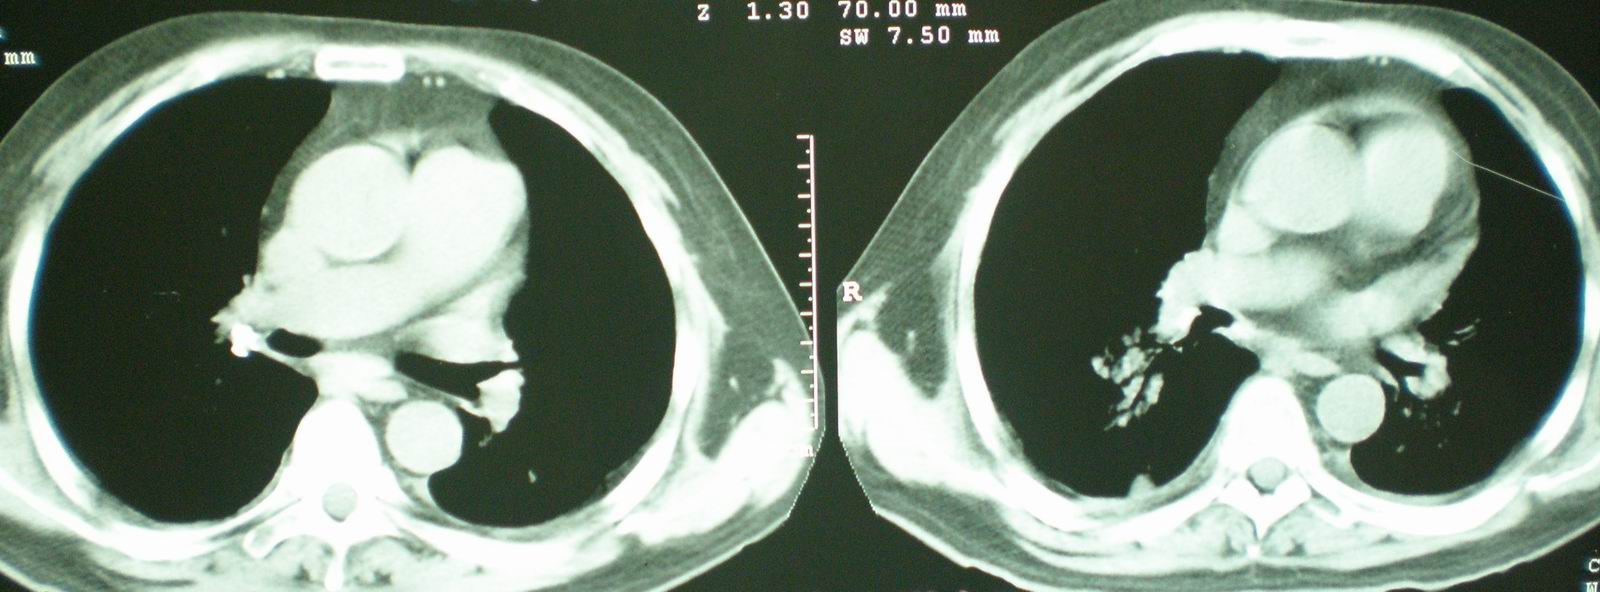

2008年11月18日今天的ct片

我仔细看了下病人的出院小结,当时情况危急,诊断里有1型呼衰。心包周围的是脂肪密度。结合三次ct扫描的图象分析,个人认为:1、病人目前肺部病灶基本消失,双侧胸腔内少量积液,抗结核治疗才一个多月,就算是结核,抗结核治疗有效果,为何效果如此好,一点纤维灶的痕迹都没有呢,再就是患者做过气管镜检查及活检、痰检均未找到结核的证据。所以不支持结核的诊断。

2、结合现在的ct片,考虑:肺水肿及真菌感染,双侧胸腔积液。